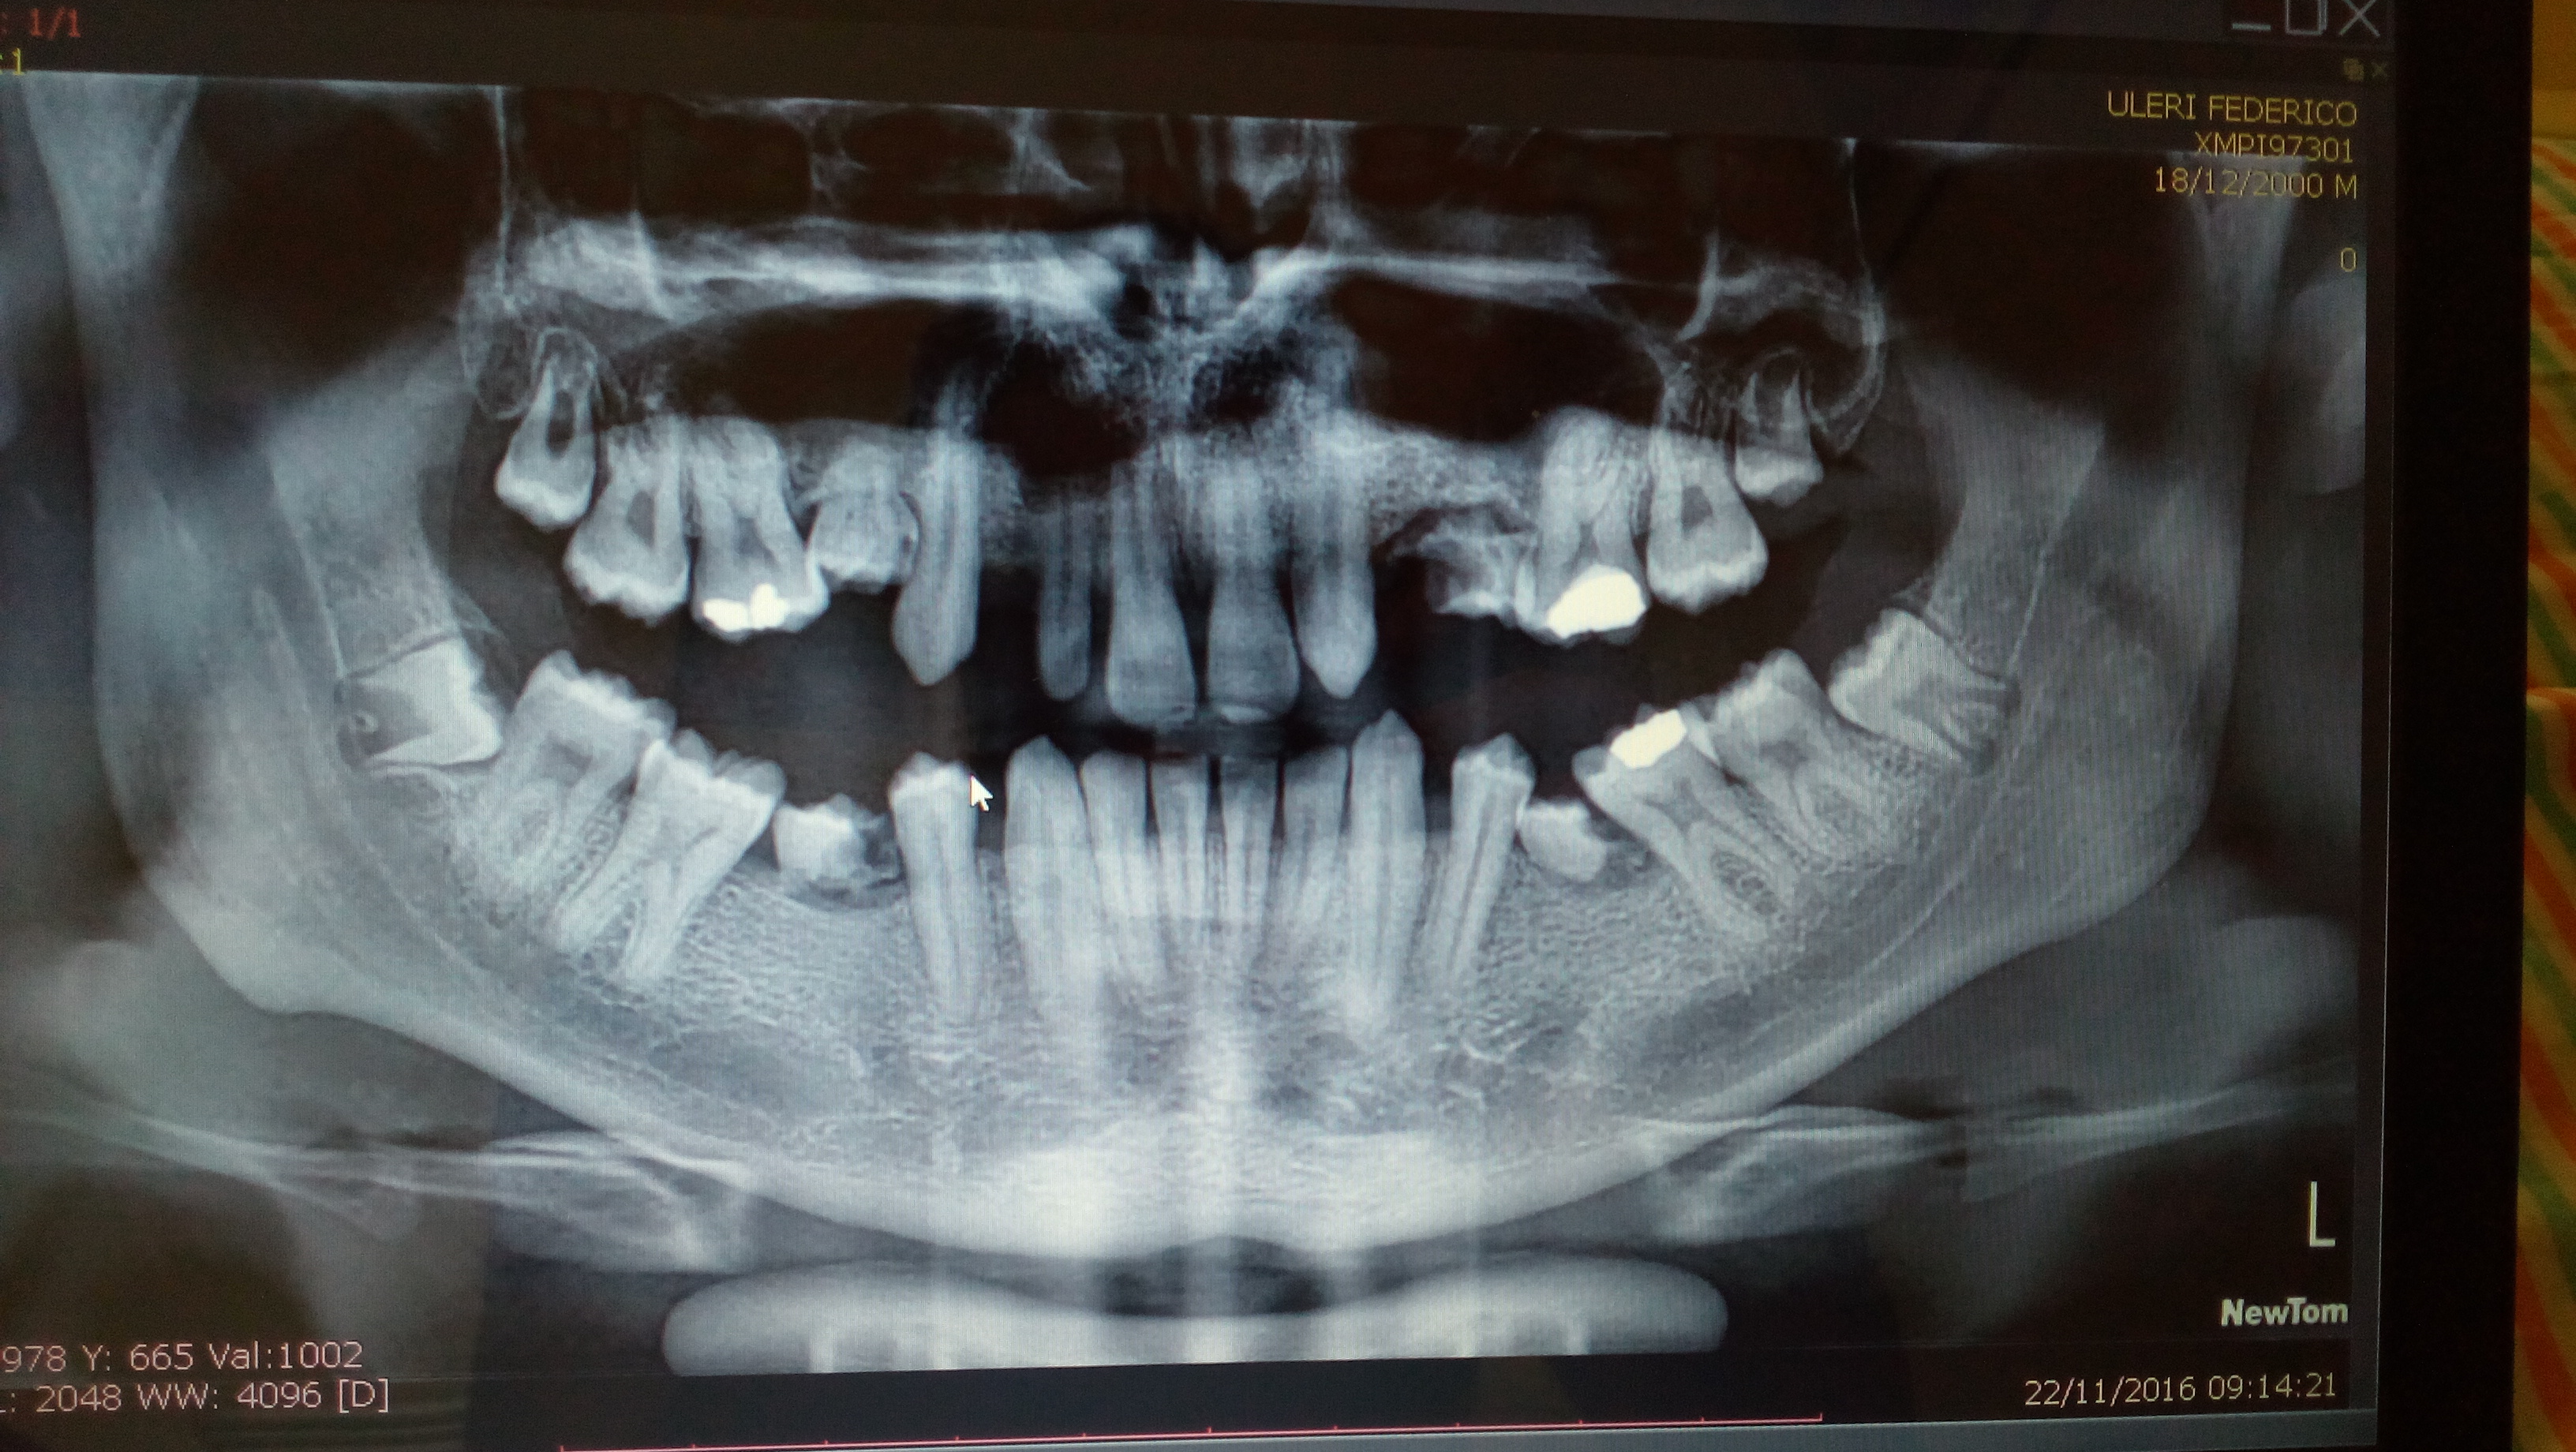

L'estrazione è la soluzione migliore?

Egregi Dottori, sono una donna di 35 anni e vi scrivo per ricevere un consiglio; a seguito di una visita con panoramica presso un centro odontoiatrico, mi è stata indicata come cura per il molare (dente nr. 27 indicato in foto allegata) l'estrazione del dente. Vorrei sapere se l'estrazione è la soluzione migliore e